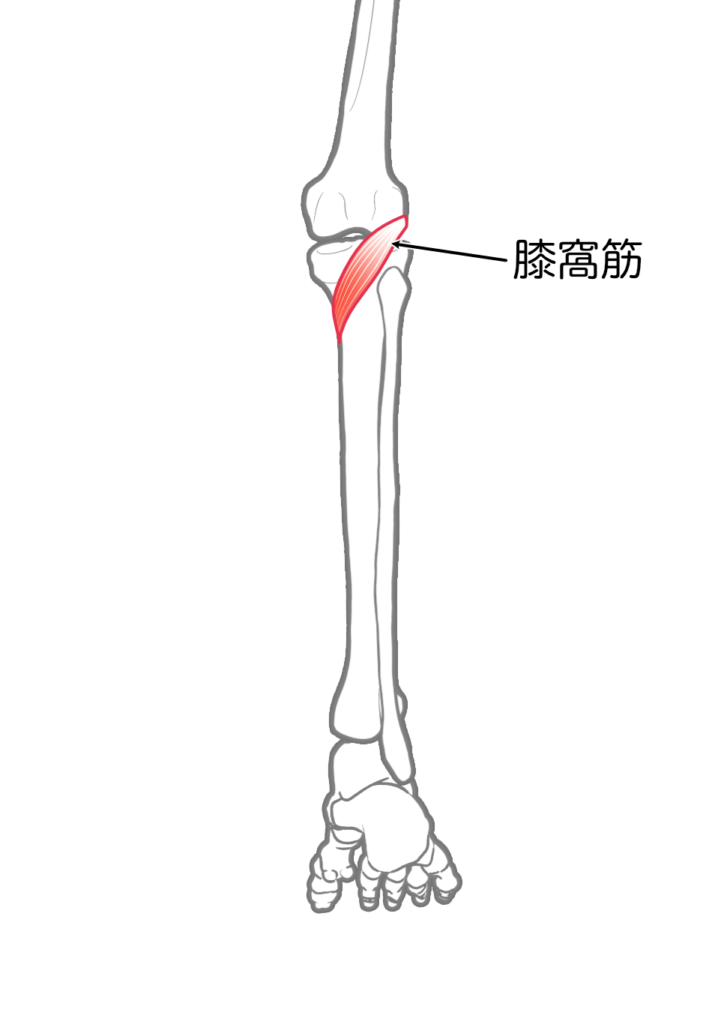

膝窩筋

| 起始 | 大腿骨外側上顆 |

| 停止 | 脛骨上部後面 |

| 神経 | 脛骨神経L4-S1 |

| 作用 | 膝関節屈曲,内旋 |

膝関節固有の筋は膝窩筋のみであることも、臨床での鑑別に役立ちます。